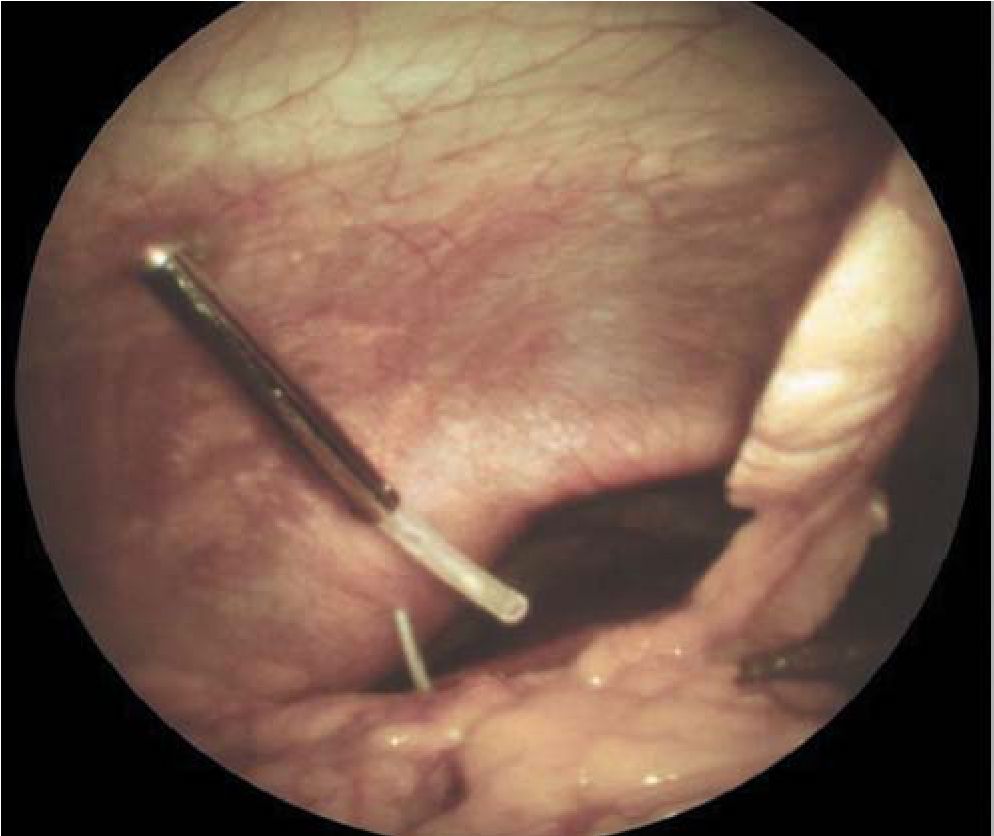

При поступлении всем 30 больным ПН произведена лечебно-диагностическая лапароскопия, шестерым выполнено наложение чрескожной чреспеченочной холецистостомы с целью декомпрессии желчевыводящих путей. Еще 3 пациентам чрескожная чреспеченочная холецистостома установлена под контролем УЗИ в более поздние сроки в связи с появлением билиарной гипертензии. Лапароскопию применяли для верификации формы, распространенности ПН, дренирования брюшной полости при ферментативном перитоните или для выполнения лапароскопической холецистостомии при гипертензии в желчных протоках и механической желтухе (рис. 2).

Рис. 2. Лапароскопическое Дренирование желчного пузыря и брюшной полости при ПН.

При лапароскопии выявляли следующие достоверные (геморрагический выпот с повышенной активностью панкреатических ферментов, пятна стеатонекроза на брюшине и большом сальнике, изменение внешнего вида ПЖ при панкреатоскопии) и косвенные (гиперемия и выбухание желудочно-ободочной связки, увеличение желчного пузыря без признаков воспаления, оттеснение желудка к передней брюшной стенке, геморрагическая имбибиция желудочно-ободочной связки, корня брыжейки тонкой кишки или забрюшинной клетчатки, парез и синюшность поперечноободочной кишки, гиперемия брюшины, изменение круглой связки печени) признаки ПН.